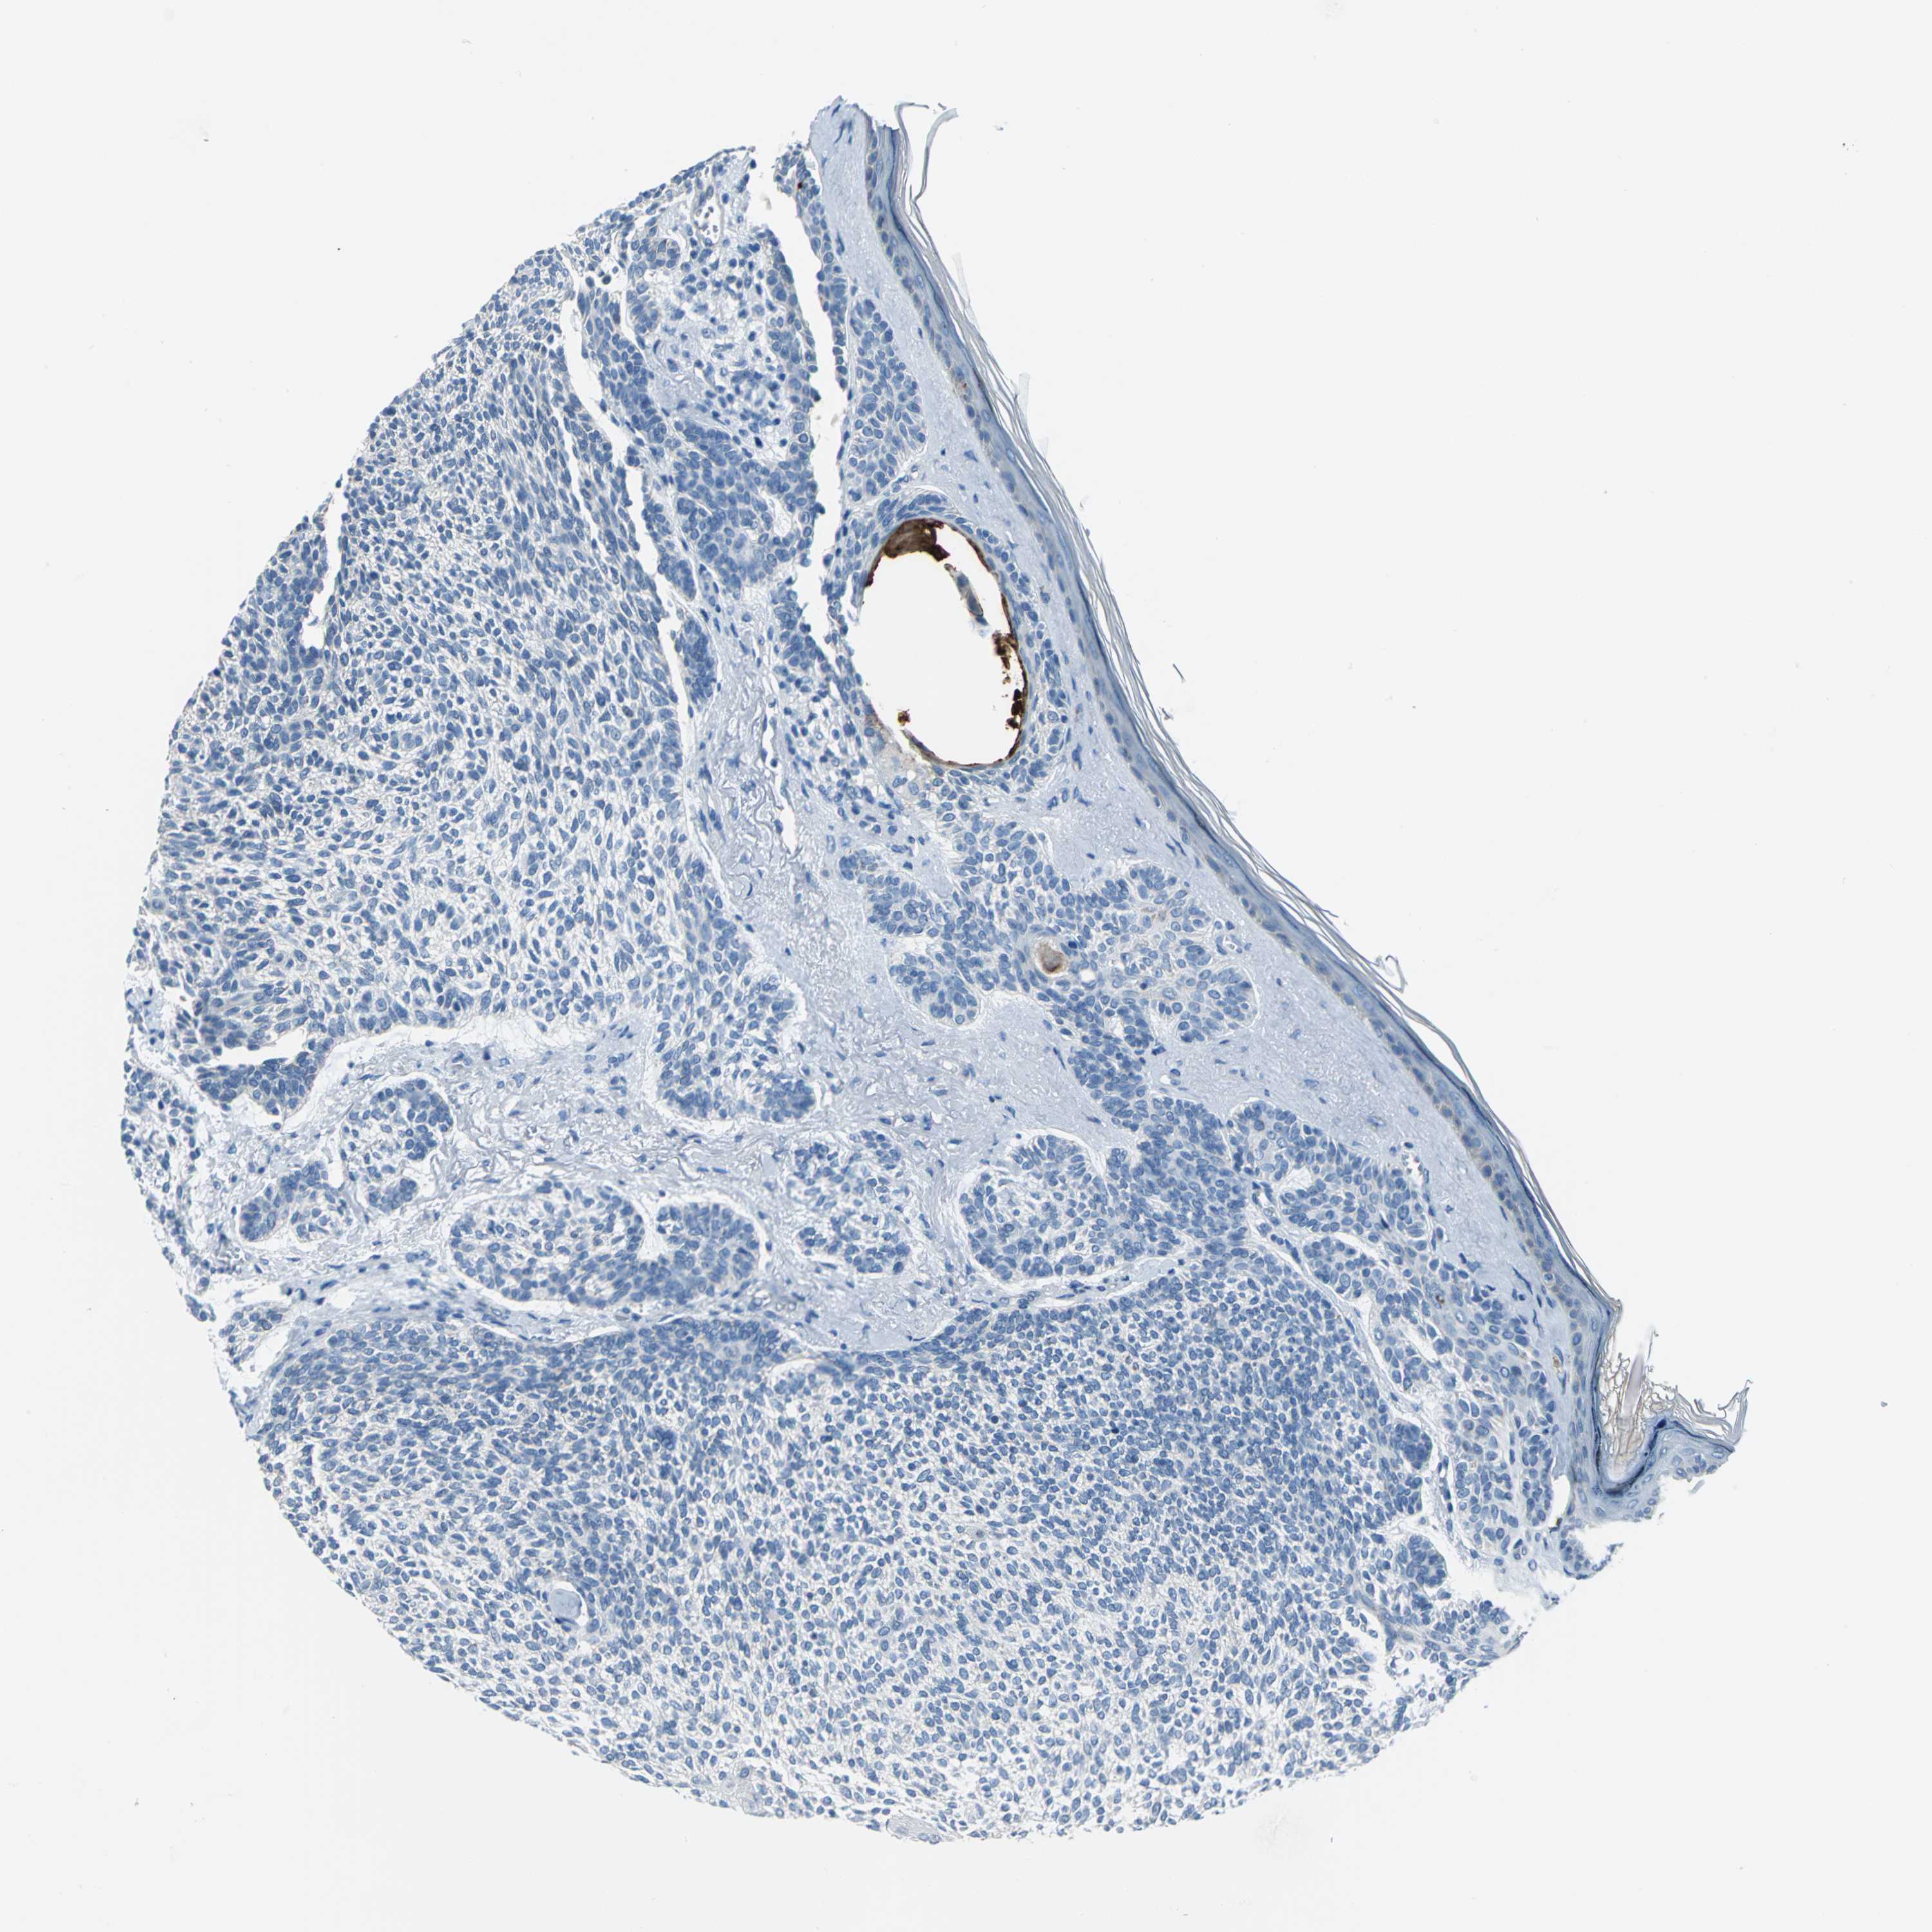

SKIN CANCER - Protein expressioni

A mouse-over function shows sample information and annotation data. Click on an image to view it in a full screen mode. Samples can be filtered based on level of antibody staining by selecting one or several of the following categories: high, medium, low and not detected. The assay and annotation is described here.

Antibody stainingi

Antibody staining in the annotated cell types in the current human tissue is reported as not detected, low, medium, or high, based on conventional immunohistochemistry profiling in selected tissues. This score is based on the combination of the staining intensity and fraction of stained cells.

Each image is clickable and will lead to virtual microscopy that enables deeper exploration of all samples and also displays staining intensity scores, fraction scores and subcellular localization as well as patient and tissue information for each sample.

Antibody HPA005895

Antibody CAB013536

Squamous cell carcinoma, NOS

Basal cell carcinoma